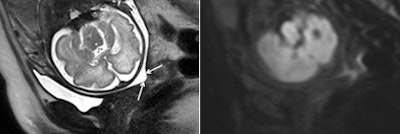

MRI scans were conducted using a 1.5-tesla scanner (Avanto, Siemens) with a 16-channel phased-array torso coil covering the entire pelvis. The women were imaged in the supine position and entered the magnet feet first to minimize any feelings of claustrophobia.

The researchers calculated ADC values from MRI of the subglandular and stromal cervix -- subglandular ADC, stromal ADC, and ADC difference -- and correlated these parameters with the time interval until delivery. Receiver operator characteristics (ROC) curve analysis was performed to determine sensitivity and specificity of the ADC values in association with delivery within seven days.